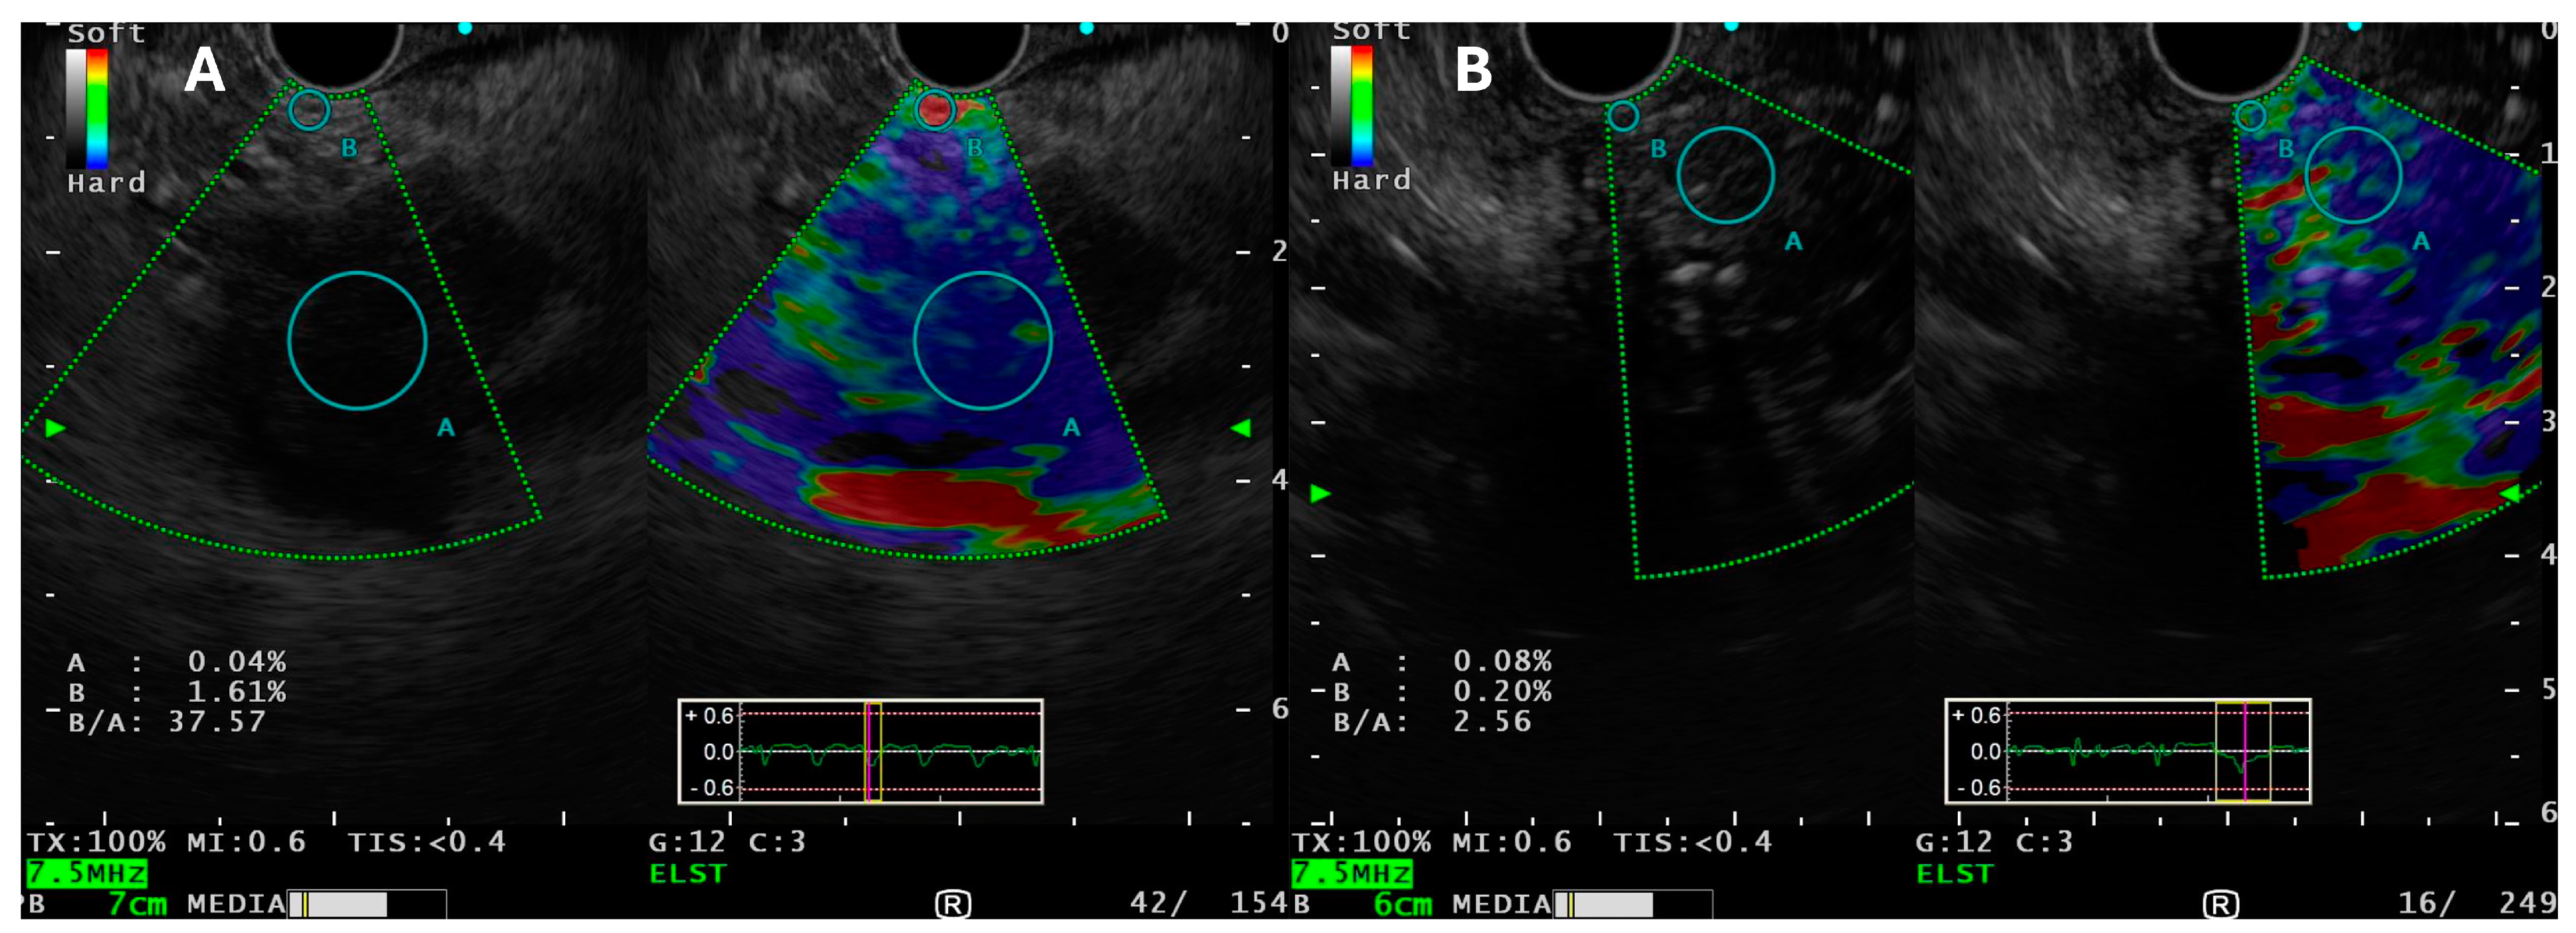

Zhang et al. reported a meta-analysis of 19 studies (1687 cases), wherein sensitivity and specificity of qualitative EUS-E was 98% and 63%, respectively, and of quantitative EUS-E was 95% and 61%, respectively. It showed that EUS-E can act as a valuable complementary tool to EUS-FNA for the differentiation of malignant pancreatic masses [40]. EUS-E can rule out malignancy with a high level of certainty if the lesion is soft [41] (Figure 3).

Figure 3.

EUS-elastography in patients with (A) pancreatic cancer (ductal adenocarcinoma) with strain ratio (37.57) and (B) with chronic pancreatitis with strain ratio (2.56) (color map denotes elasticity of the tissue: red for soft tissue, green for intermediate-hard tissue, and dark blue for hard tissue).

Despite ample publications on the use of EUS-E for SPL characterization, data are extremely sparse on EUS-E guided FNA/B versus standard EUS-TA for pancreatic masses. The authors analyzed four studies comparing the same (three prospective and one RCT) for EUS-TA for SPL (Supplementary Table S4). Only 2 (Nayak et al. and Gheorghiu et al.) studies reported EUS-E guided FNA/B for SPL in comparison with standard B-mode EUS FNA [42,43]. Both studies negated any positive benefit of EUS-E guided FNA over standard practice of tissue acquisition. Moreover, only FNA was used, instead of FNB for TA.